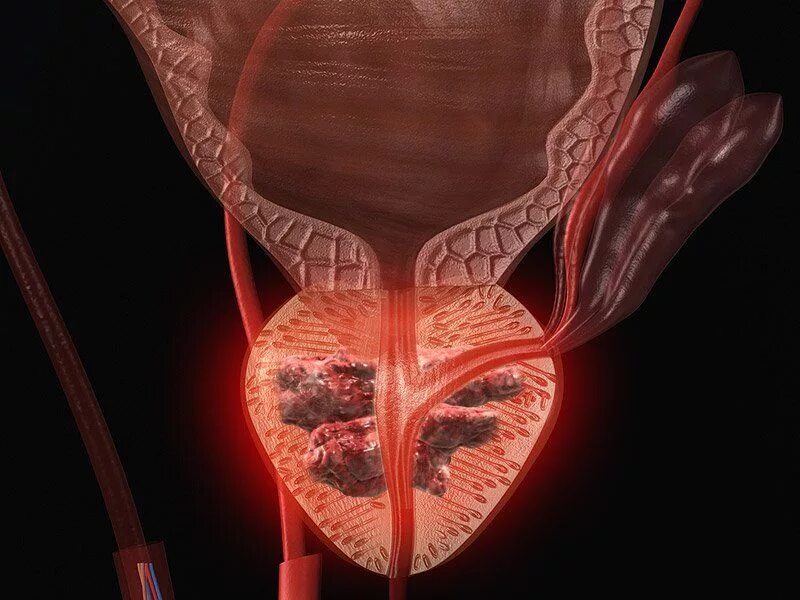

Опухоль аденомы простаты симптомы. Раковые заболевания простаты. Раковая опухоль простаты. Предстательная железа у мужчин онкология Злокачественная опухоль простаты. Злокачественное новообразование предстательной железы. Злокачественные новообразования простаты

Злокачественная опухоль простаты. Злокачественное новообразование предстательной железы. Злокачественные новообразования простаты Карцинома предстательной железы. Злокачественное новообразование предстательной железы. Cancer предстательной железы. Аденома предстательной железы – это опухоль

Опухоль предстательной железы. Карцинома предстательной железы. Злокачественное новообразование предстательной железы. Объемное образование предстательной железы Предстательная железа 3д. Опухоль предстательной железы. Злокачественные новообразования простаты. Карцинома предстательной железы

Предстательная железа 3д. Опухоль предстательной железы. Злокачественные новообразования простаты. Карцинома предстательной железы Карцинома предстательной железы. Что такое РПЖ предстательной железы. Онкология предстательной железы. Злокачественное новообразование предстательной железы